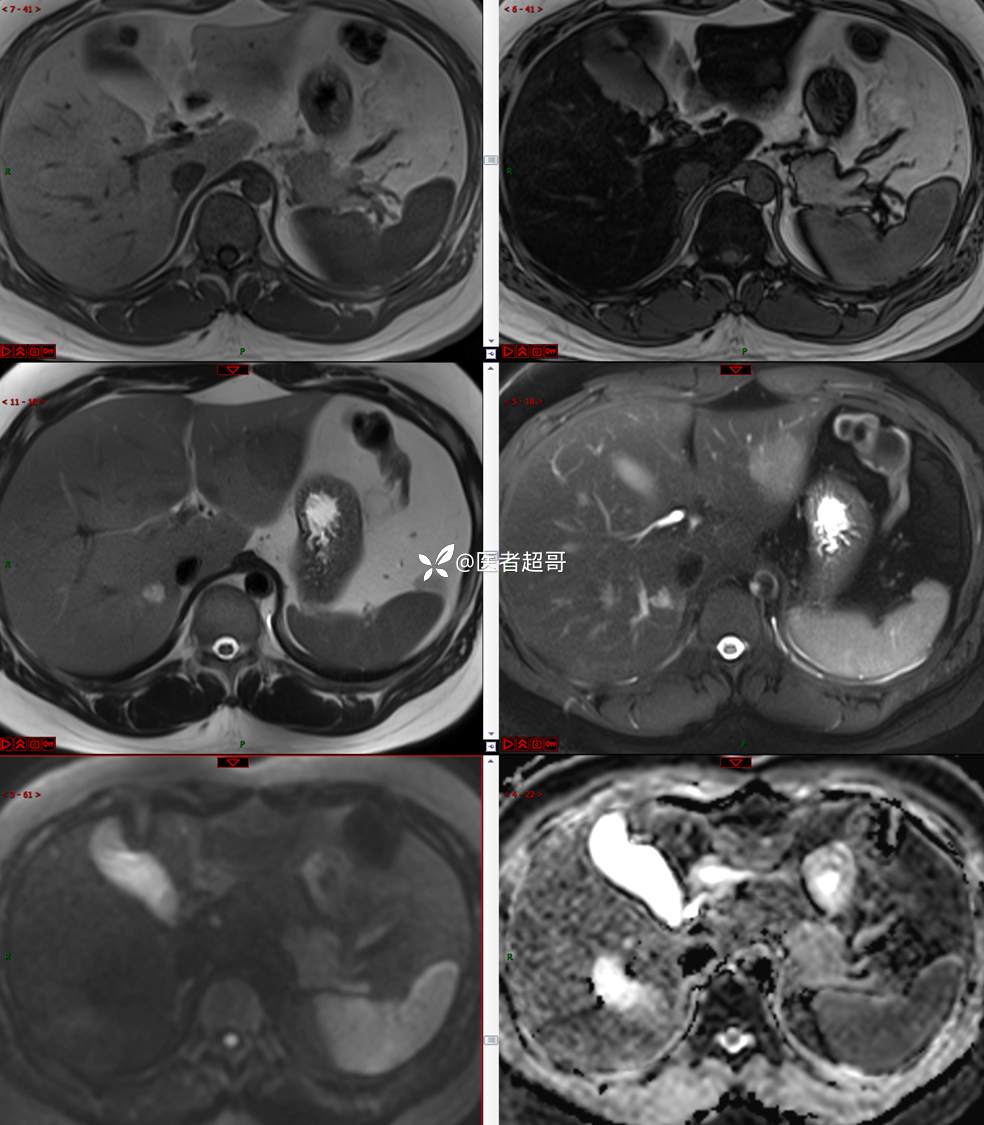

【影诊笔记685】男,31y,发现肝占位性病变5天就诊,请诊断分析,有病理结果!

主 诉:发现肝占位性病变5天。

现病史:患者缘于5天前体检时发现肝占位性病变,未予以特殊处置。现患者为求系统诊治就诊于我院,行普美显提示:肝左叶富血供占位,请结合临床及其他检查,肝多发血管瘤,脂肪肝,肝囊肿,请结合临床。门诊以“肝占位性病变”收入我科。病程中,饮食睡眠可,二便可,近期体重未见明显变化。